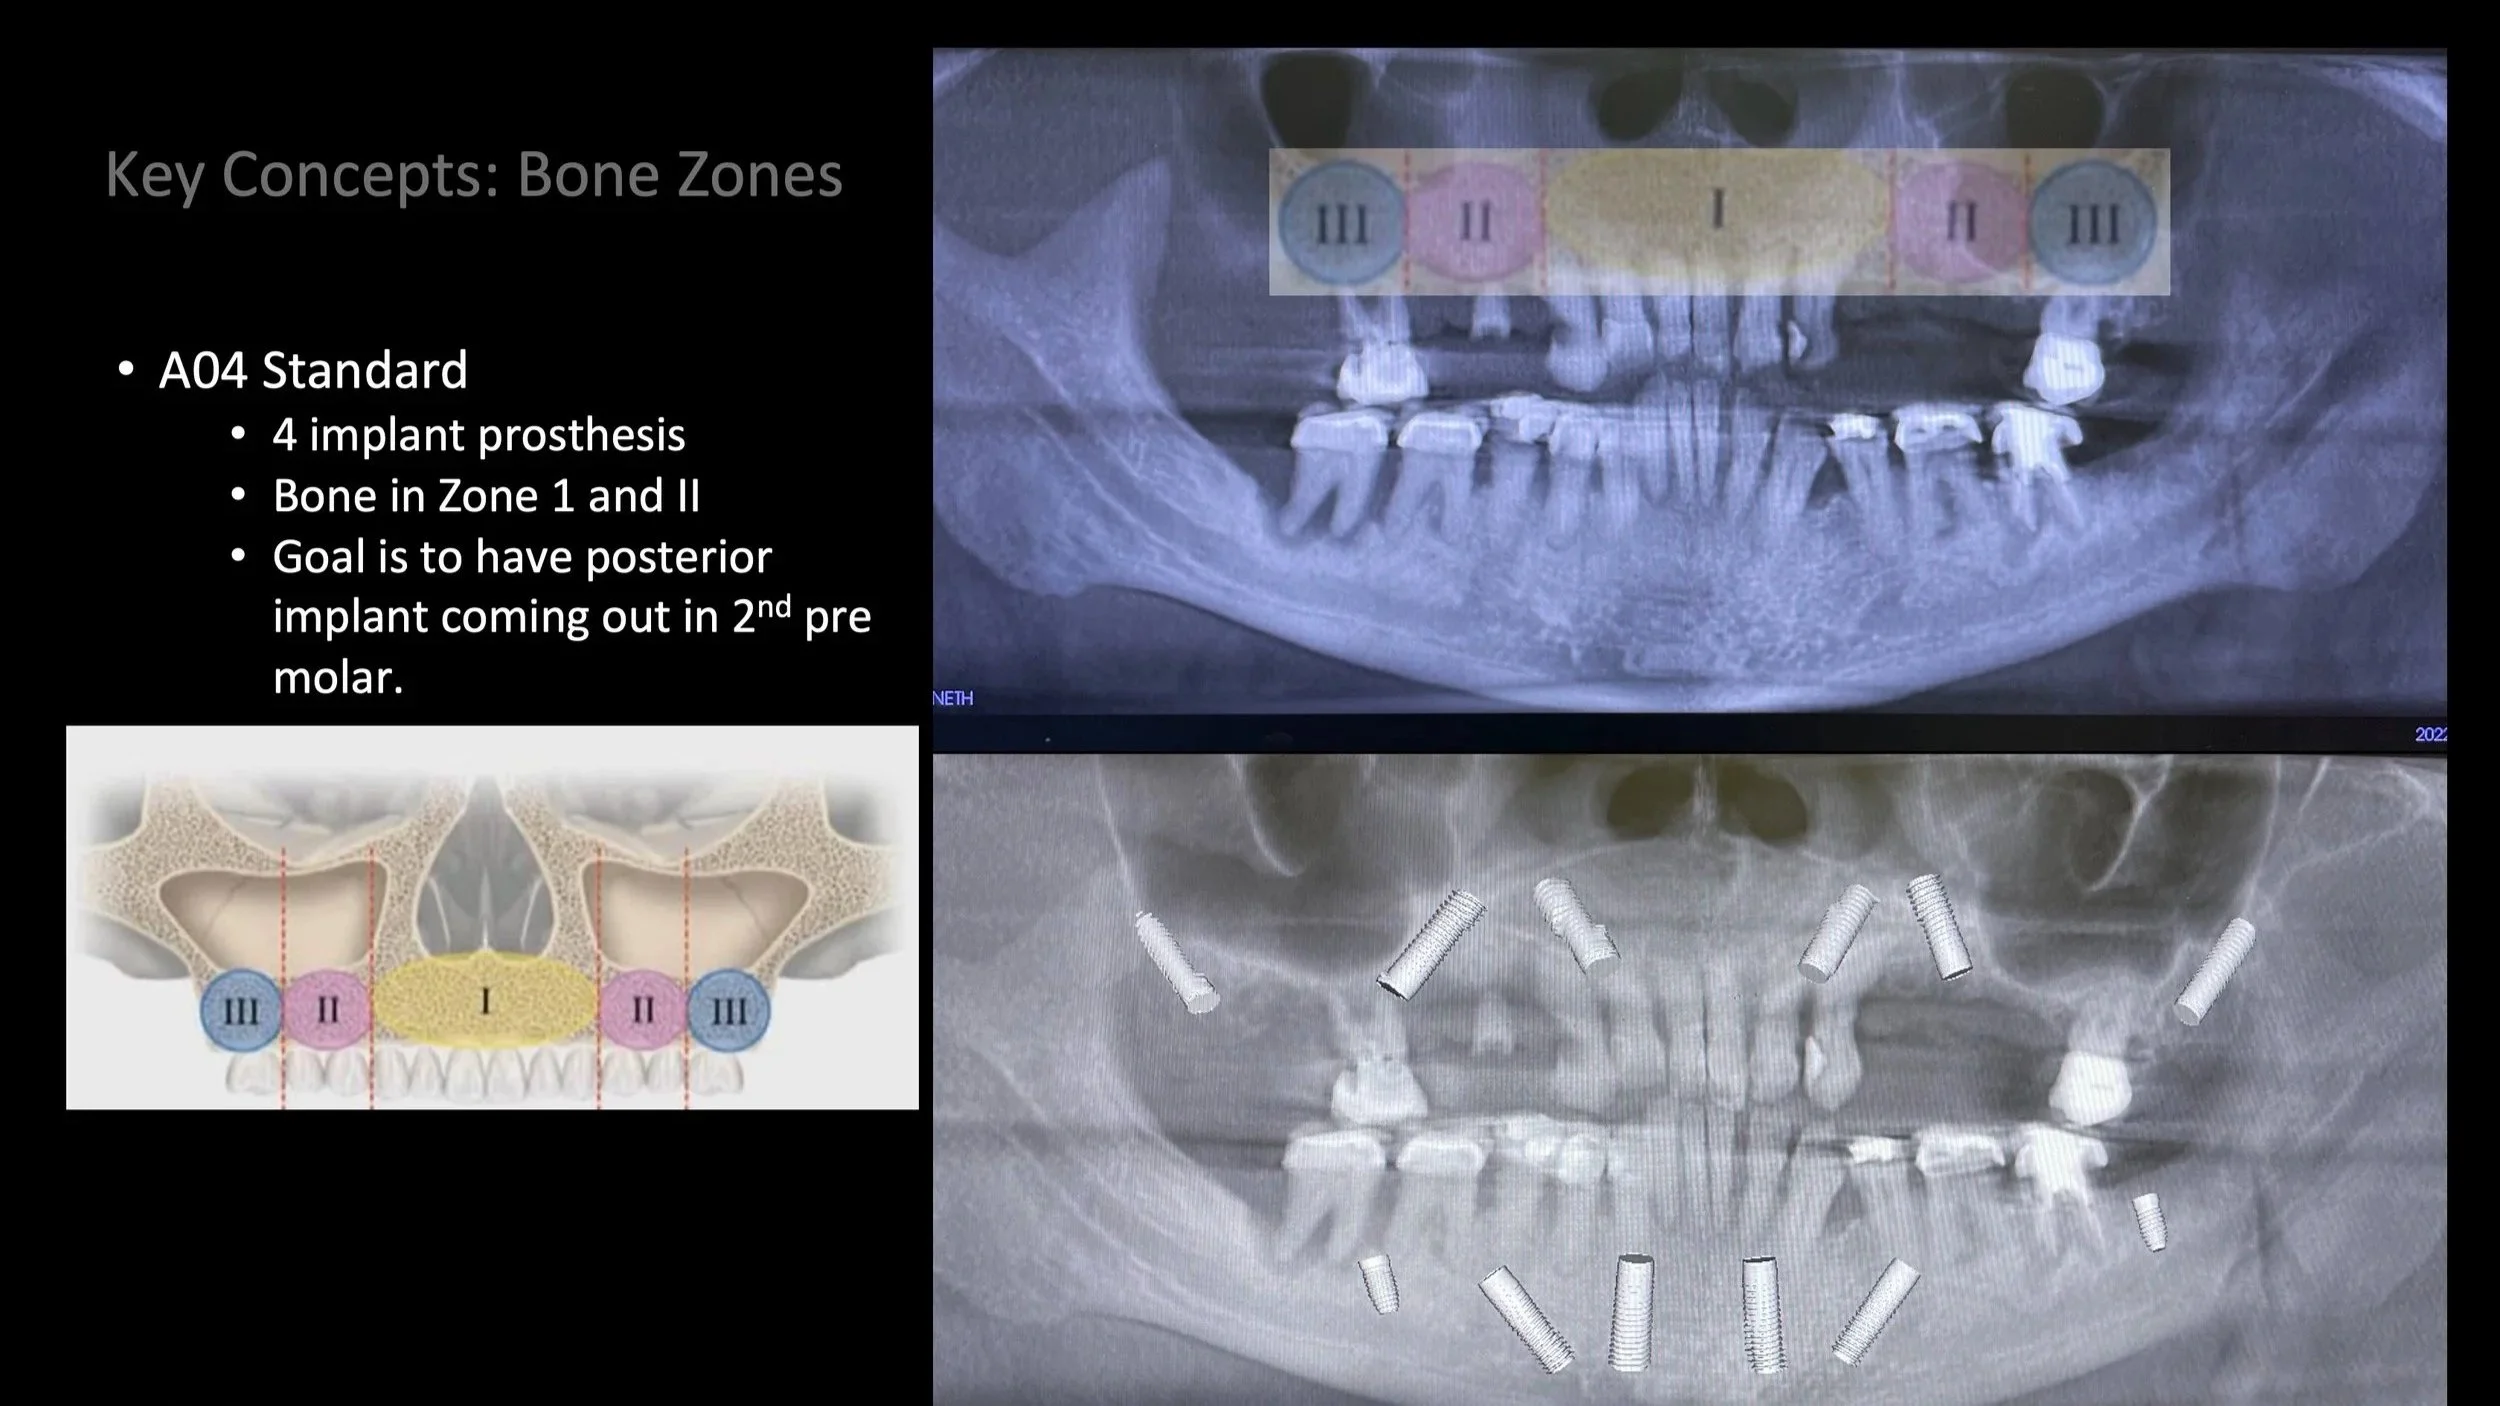

Case Selection

Dr. Damon will highlight the “Red Flags” of full arch, one of them being when the sinus extends anteriorly and touches the canine roots. We will discuss proper case selection, but also get you ready to take your next step in Full Arch—with remote anchorage.